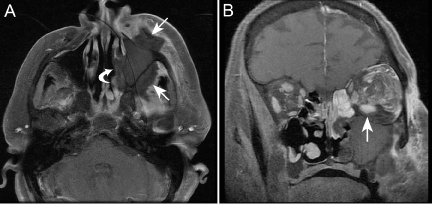

| Figure 1: MR imaging of a 58-year-old female (Case 1) with AFIFS. (A) Axial T1 MR with gadolinium and fat saturation demonstrates soft tissue swelling of the left cheek and opacification of the left maxillary sinus. Note, however, loss of contrast enhancement (LoCE) of the wall of the sinus, of the soft tissues anterior and posterior to the sinus (arrows), and of the nasal cavity lateral wall (curved arrow). LoCE of tissues is believed to correlate with tissue necrosis. (B) Coronal T1 MR with gadolinium and fat saturation shows extensive LoCE of the left maxilla and perimaxillary tissues, but also LoCE of the inflamed retrobulbar fat and periphery of the inferior rectus muscle (arrow). Normal extraocular muscles enhance on gadolinium-enhanced T1 MR. |